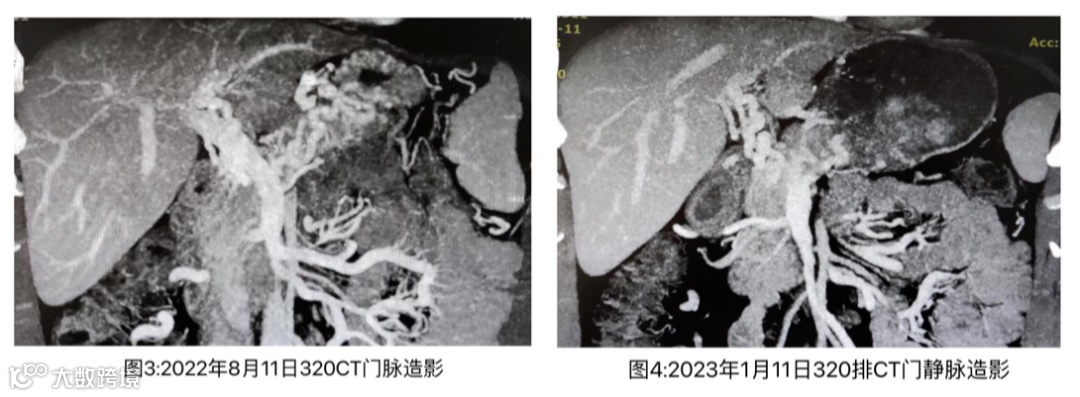

2022年2月10日患者开始于我院随访,2022年8月10日 320 CT门静脉造影提示门静脉右上分支充盈差,相应区域见条状低密度影,胃底及肝门区多发迂曲血管影,脾脏稍大(图3),随访过程中观察患者凝血、血常规等指标,可见患者血红蛋白(波动于170-178 g/L)、红细胞(波动于5.61-5.92×1012/L)均属于一个正常范围高限,但凝血四项、D-二聚体等凝血指标未见明显异常。D-二聚体:0.06 mg/L,纤维蛋白(原)降解产物:0.3 mg/L。2022年9月,患者因手外伤后愈合缓慢咨询医生后调整用药为利伐沙班10 mg/次 1次/日。

2023年1月主因“发现门静脉广泛血栓1年”,行肠道息肉切除术入住我科。入院查体:神志清楚,正常面容,皮肤巩膜无黄染,未见蜘蛛痣及肝掌,腹部软,未见腹部静脉曲张,全腹无压痛、反跳痛及肌紧张,肝脾肋下未及。余未见特殊阳性体征。完善检查:血常规:白细胞: 6.66 x109/L,红细胞:5.78 x1012/L,血红蛋白:172 g/L,红细胞比容:52.5%,血小板:204×109/L;D-二聚体:0.06 mg/L,凝血酶原时间:13 S,凝血酶原活动度:70%,国际标准化比率:1.13,纤维蛋白原:2.33 g/L,活化部分凝血活酶时间:30 S,凝血酶时间:17.6 S,抗凝血酶Ⅲ:103.2 g/L,纤维蛋白(原)降解产物:0.3 mg/L;我院胃镜提示胃底见2条曲张静脉(图5),其中1条延申至胃体上段大弯,最粗直径0.4 cm,RC-;320排腹部CT(图4)提示门静脉右上分支充盈差,相应区域见条状低密度影,提示拴子可能,较前变化不明显,门静脉左支欠清,胃底及肝门区多发迂曲血管;2、肝内钙化灶;3、脾脏稍大;肝纤维化无创检测示:FibroScan 9.1kPa(未到达肝硬化诊断标准)。患者行内镜息肉切除术后,无消化道出血情况,无不适症状遂出院。